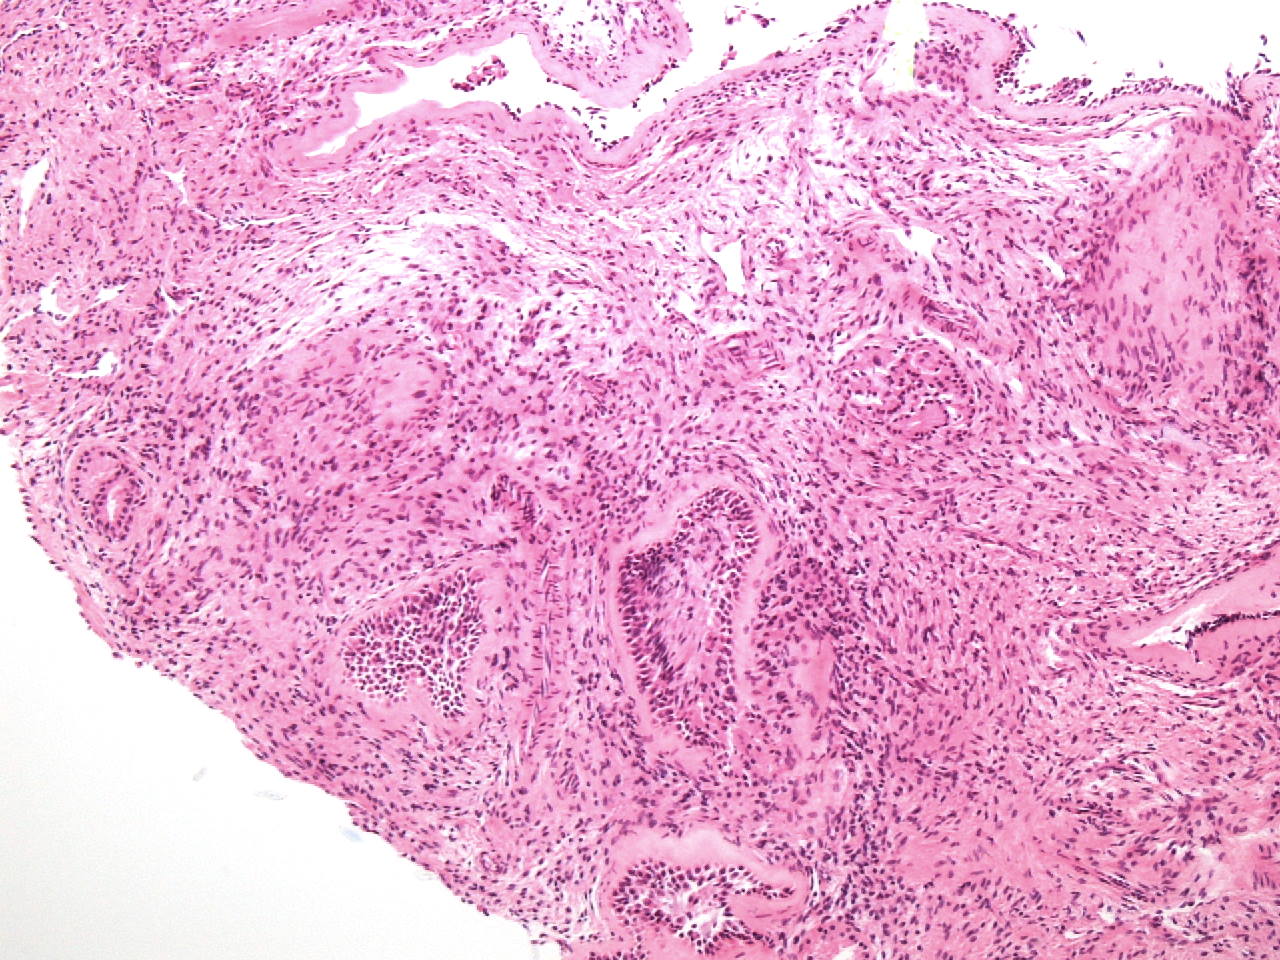

Case history: 17-year-old female with large, solid adnexal mass.

What is the diagnosis?

- Germ cell ...